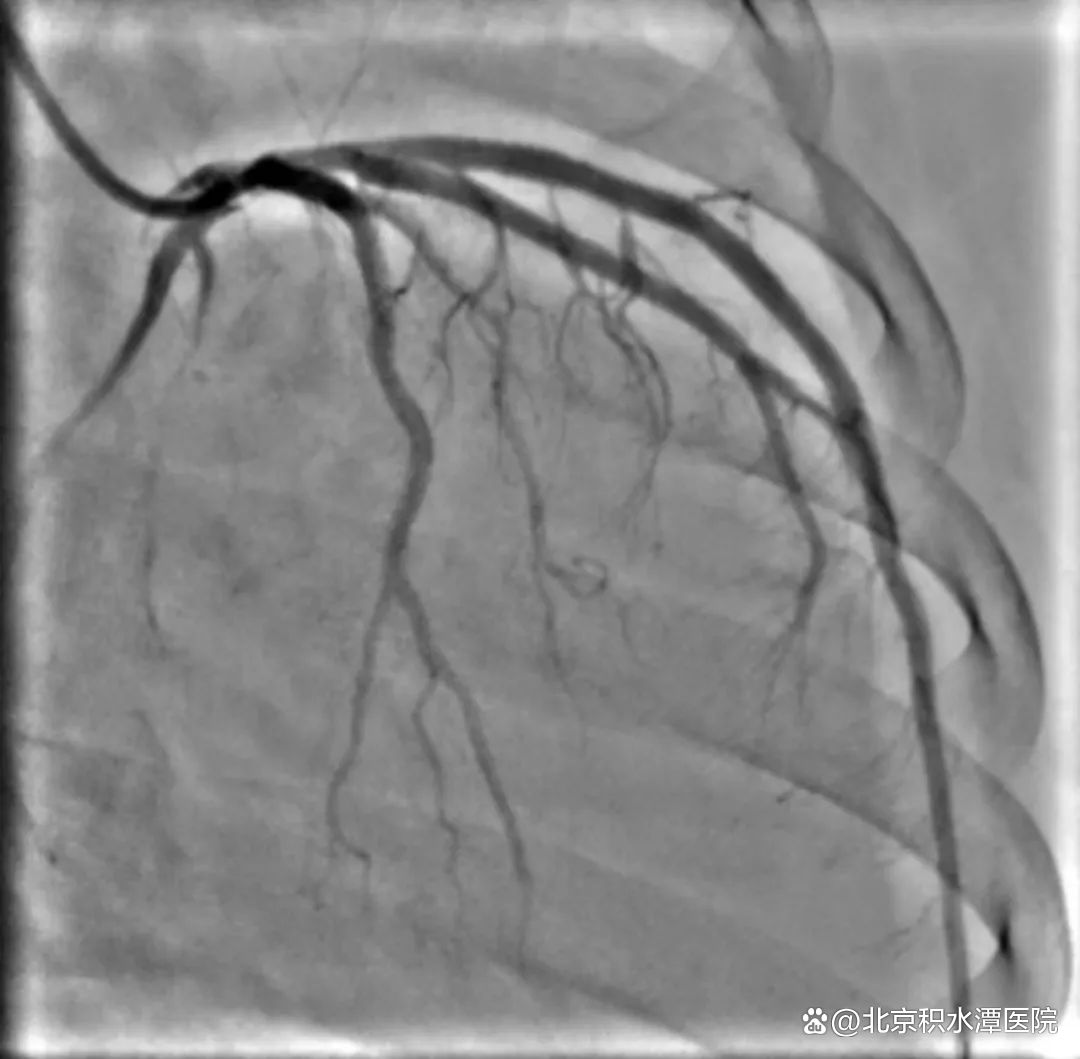

转运途中,患者突发室颤,经过医护人员除颤和抢救,患者才恢复意识。抵达新龙泽院区后,医院立即启动了急性心梗抢救团队,专家们进行了紧急会诊和手术准备工作,患者被紧急送往导管室,通过急诊介入手术(PCI)进行了血管再通。手术过程中,由于再灌注损伤,术中心脏室颤再次发作,医生们沉着冷静进行除颤和抢救,心律稳定后,成功地为患者疏通了被堵塞的血管,改善了心肌缺血现象,挽救了患者生命。